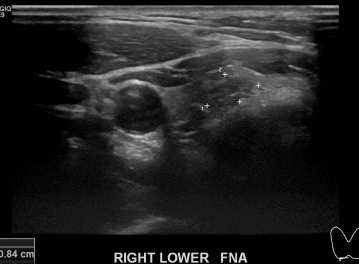

상기환자  외부 건진상 이상소견으로 내원하신 30대중반 남성분으로 의심스러운 갑상선 우엽 결절 세포검사진행후 갑상선암으로 진단되었습니다